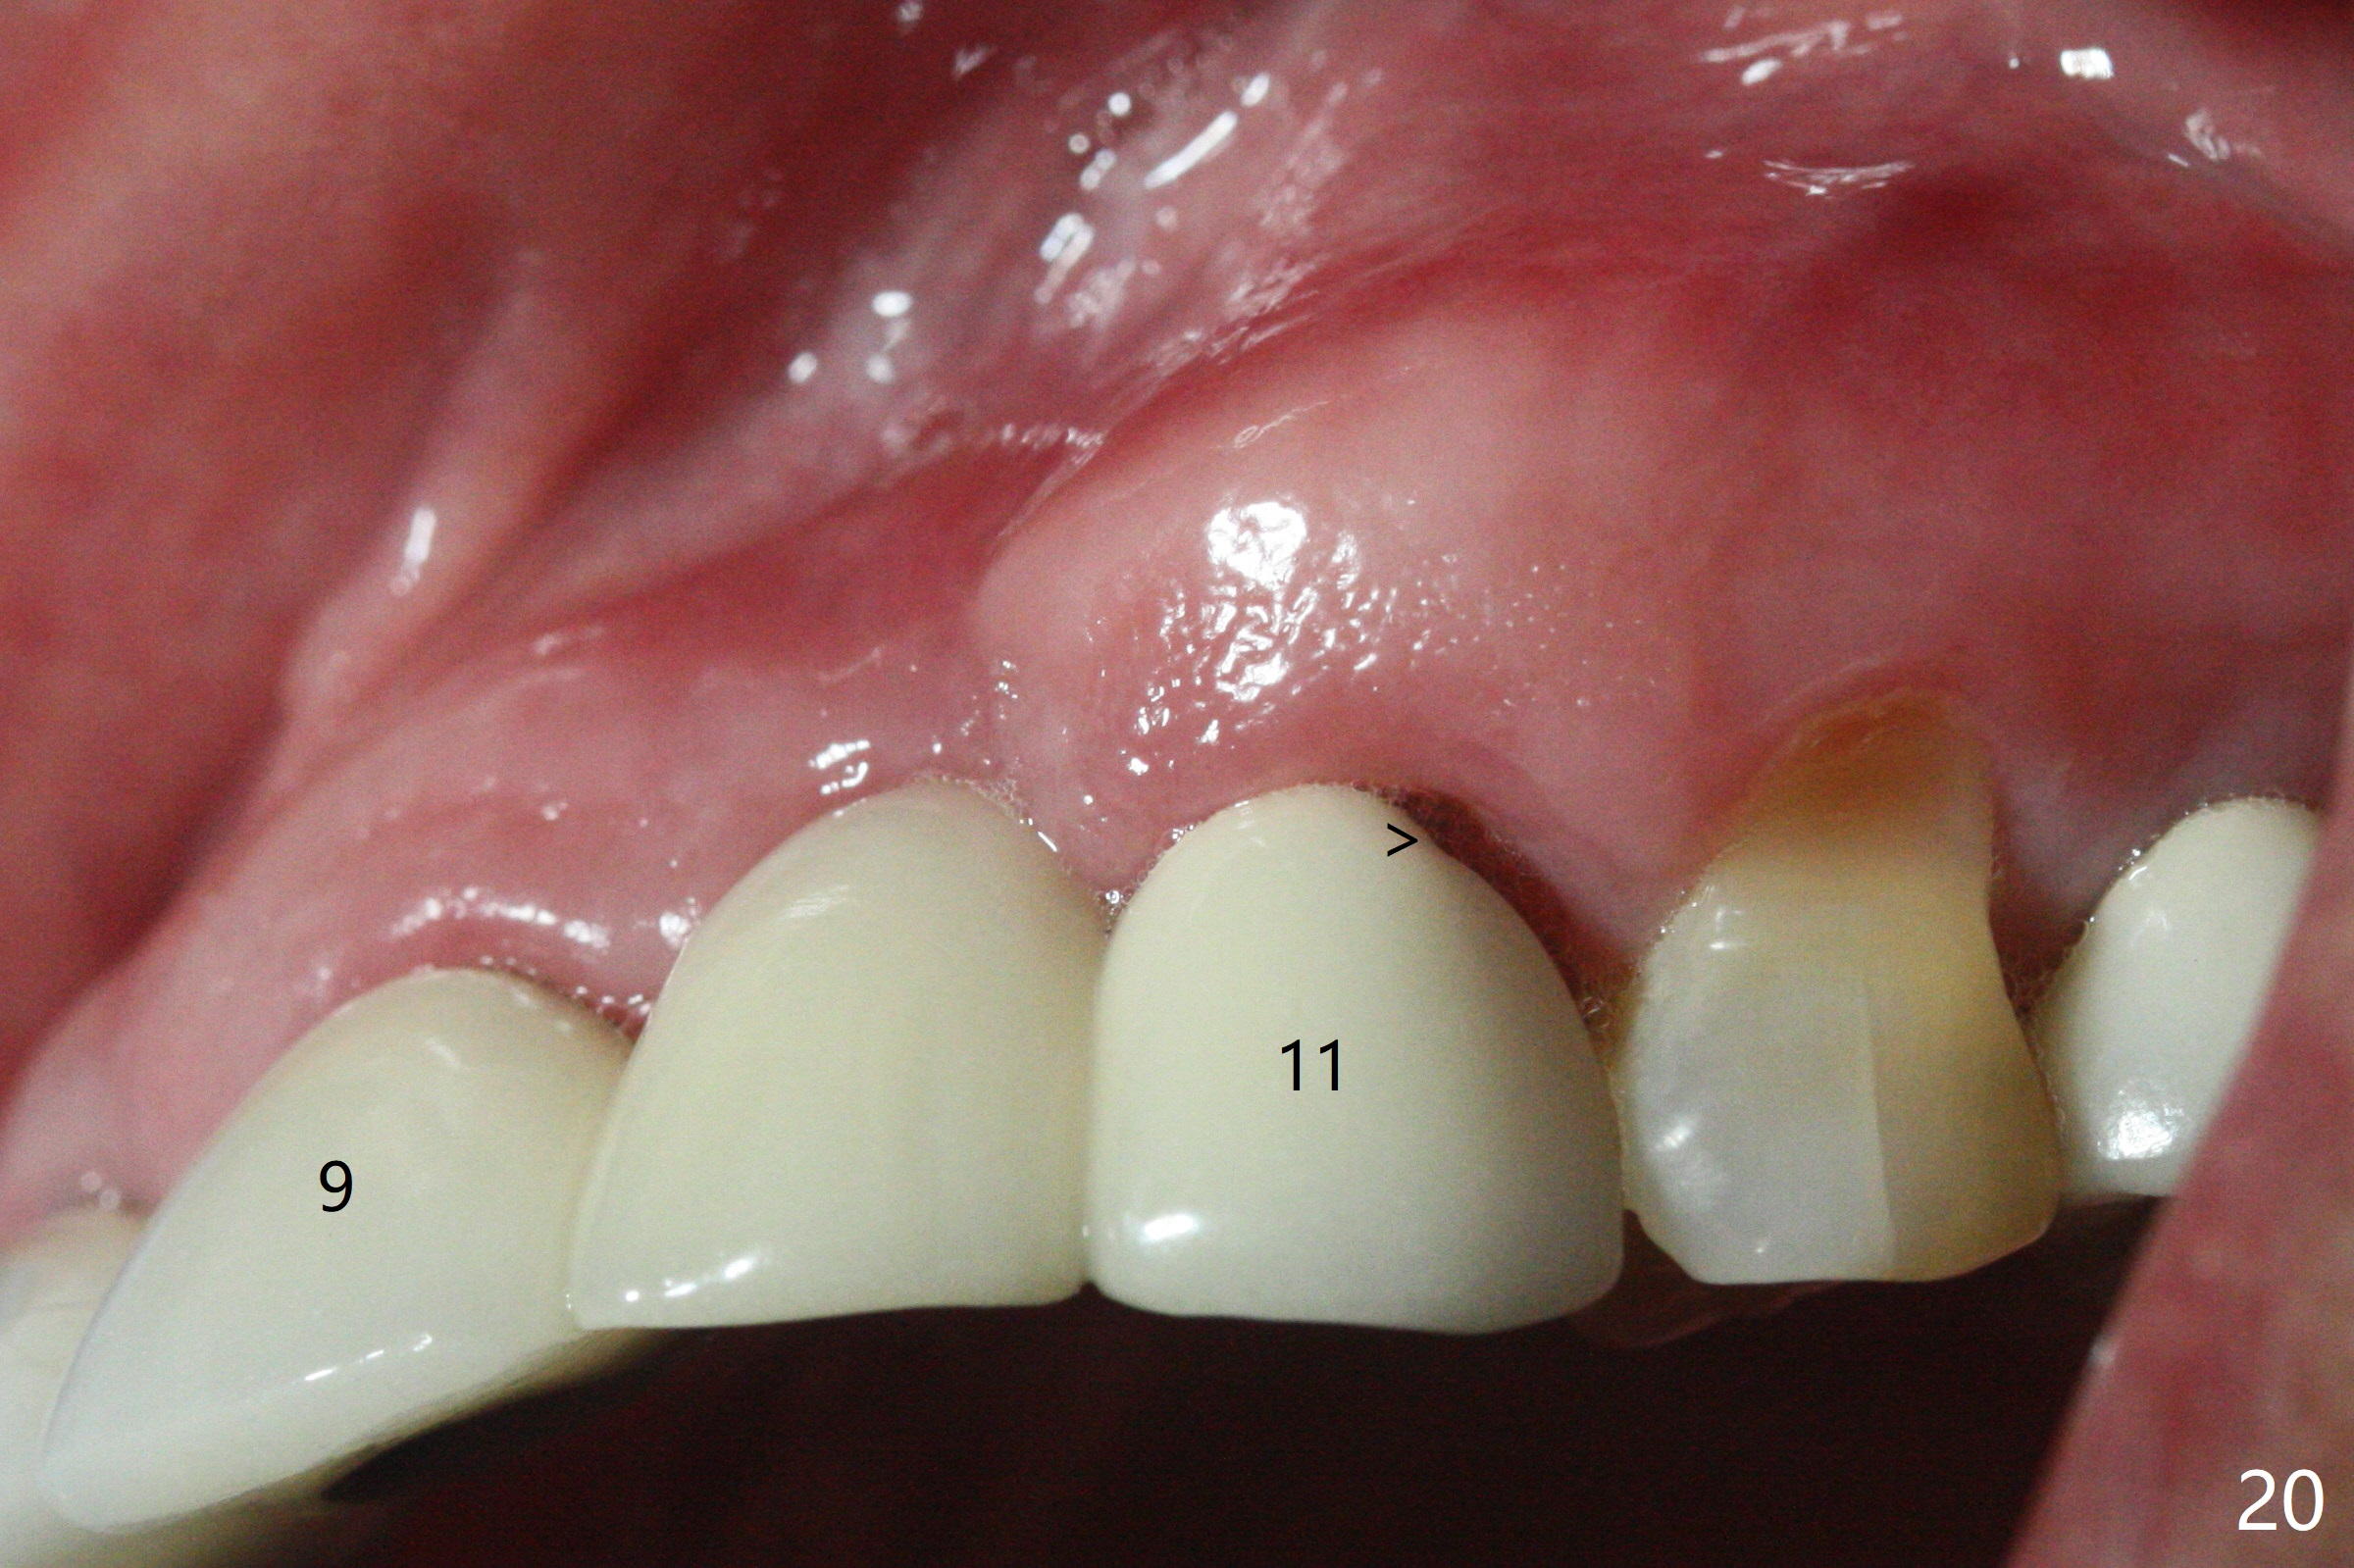

In brief, bone expanders or osteotomes can be used for bone expansion and condensation to improve primary stability of implant placement. No bone graft appears to be needed. The buccal concavity remains minimal 6 years post cementation (Fig.18). In fact he is a bruxer with torus palatinus (Fig.19). The bridge of #9-11 is loose because of subgingival fracture of the abutment of #11 for 2.5 years (Fig.20).